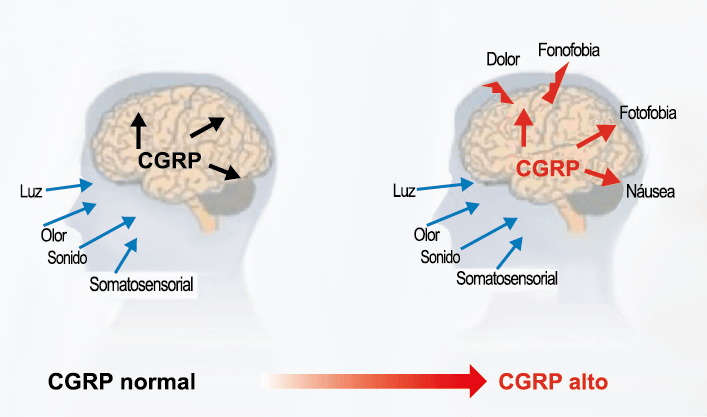

Péptido relacionado con el gel de la calcitonina (CGRP por sus siglas en inglés)

El CGRP (Péptido relacionado con el gel de la calcitonina) es un neuropéptido de 37 aminoácidos con potentes efectos vasodilatadores que se produce mediante empalme alternativo del gen de la calcitonina. Con respecto al sistema nervioso, αCGRP se expresa predominantemente, mientras que βCGRP se asocia con el sistema sensorial entérico(64). El CGRP actúa en dos receptores: uno, el llamado complejo canónico de CGRPreceptor, está formado por un receptor acoplado a proteína G y un único receptor transmembrana que modifica proteína (RAMP) 1(65).

RAMP 1 es fundamental para el transporte y la expresión en la superficie celular del complejo del receptor CGRP y su sobreexpresión da como resultado fenotipos similares a la migraña, incluida la aversión a la luz y la alodinia inducida por CGRP(66) (Figura 32 y 33).

El CGRP está ampliamente distribuido, incluso en el cuerpo estriado, la amígdala, el hipotálamo, el tálamo, el tronco encefálico y el TCC(69). Dentro de las vías trigeminovasculares aferentes primarias, la expresión de CGRP es más alta en el ganglio del trigémino sensorial y sus proyecciones de fibras Aδ y C a los vasos sanguíneos cerebrales y durales, así como centralmente a la médula espinal(70), donde puede afectar proyecciones ascendentes de segundo orden. Se han identificado receptores de CGRP funcionales y sitios de unión en las células del músculo liso de la arteria dural y en los ganglios del trigémino, el tálamo, el hipotálamo, la amígdala, la corteza y el tronco encefálico(71).

El CGRP es un potente vasodilatador que, cuando se administra a personas que padecen migrañas, se sabe que desencadena ataques(72). Se libera durante los ataques espontáneos(73) o provocados(74), que pueden inhibirse mediante el tratamiento con triptanos(75). Además de sus efectos vasculares, CGRP se ha convertido en un modulador clave de la función neuronal, que tiene efectos importantes en los sistemas de neurotransmisores como el sistema glutamatérgico(76). Sobre la base de los datos clínicos(77), se inició un esfuerzo para desarrollar antagonistas de los receptores de CGRP: los “gepantes”: telgacepant demostró una eficacia mejor que el placebo y comparable a los triptanos(78), como el primer antagonista oral del receptor de CGRP con excelente tolerabilidad a largo plazo(79) y también fue bien tolerado en pacientes que estaban siendo investigados por enfermedad arterial coronaria(80). Sin embargo, el desarrollo de telgacepant se detuvo cuando surgieron problemas con las enzimas hepáticas en un estudio preventivo, que resultó bastante positivo(81). Este efecto no se ha informado con rimagepant(82) Los ditanes, tienen como mecanismo el ser agonistas selectivos del receptor 5-hidroxitriptamina tipo 1F (5-HT1F) en la vía trigeminal, hasta ahora ha demostrado no tener efecto vasoconstrictor asociado. Lasmiditán ha sido hasta la fecha de elaboración de esta revisión la primera molécula aprobada por FDA. (Figura 35)

Los anticuerpos monoclonales contra el péptido CGRP y el receptor (numab y nezumabs) se han desarrollado para capitalizar los efectos antimigrañosos comprobados del bloqueo de los mecanismos CGRP como nuevos tratamientos preventivos. Los anticuerpos contra el péptido CGRP, al CGRP y del receptor CGRP (complejo CLR/RAMP1) han presentado datos positivos de ensayos controlados.(83) (Figura 36 y Tabla 3)